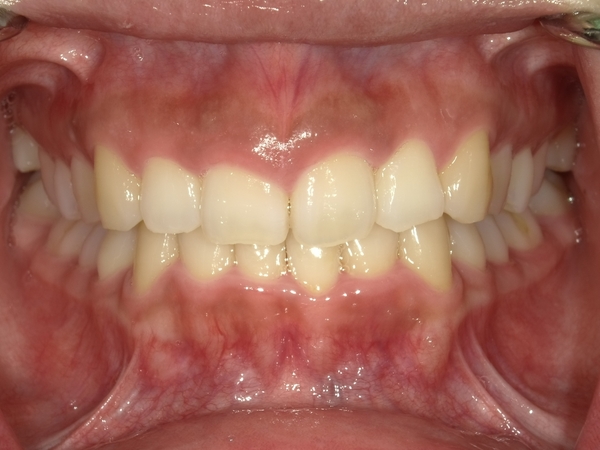

ガタガタとした歯並びや八重歯(叢生)CASE51